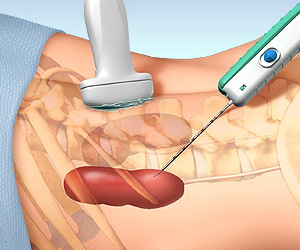

BÖBREKTEN PARÇA ALMA (BİYOPSİ)

Böbrek hastalığının nedenini anlamak için böbrekten parça almak gerekebilir. Parça almak deyince hastanın aklına genellikle kanser gelir. Nefroloji pratiğinde ise parça almanın amacı çoğu kez kanser değildir. Günümüzde ultrasonografi yardımı ile böbrekten parça almak oldukça kolay bir işlemdir ve riskleri çok azalmıştır. Özel durumlarda böbrek biyopsisi açık veya laparoskopik yapılabilir.

Böbrek biyopsisinin başlıca riskleri kanama ve ağrıdır ancak gerekli ön hazırlıktan ve işlem sonrası yakın takiple ultrasonografi yardımı ile biyopsi yapılması bu riskleri minimuma indirmiştir. Biyopsinin riskleri olduğu doğrudur ama biyopsi yapmamanın da riskleri vardır. Biyopsi zaten hastaya yararlı olabilecek bir tedavi seçeneği olduğu zaman gündeme gelir.